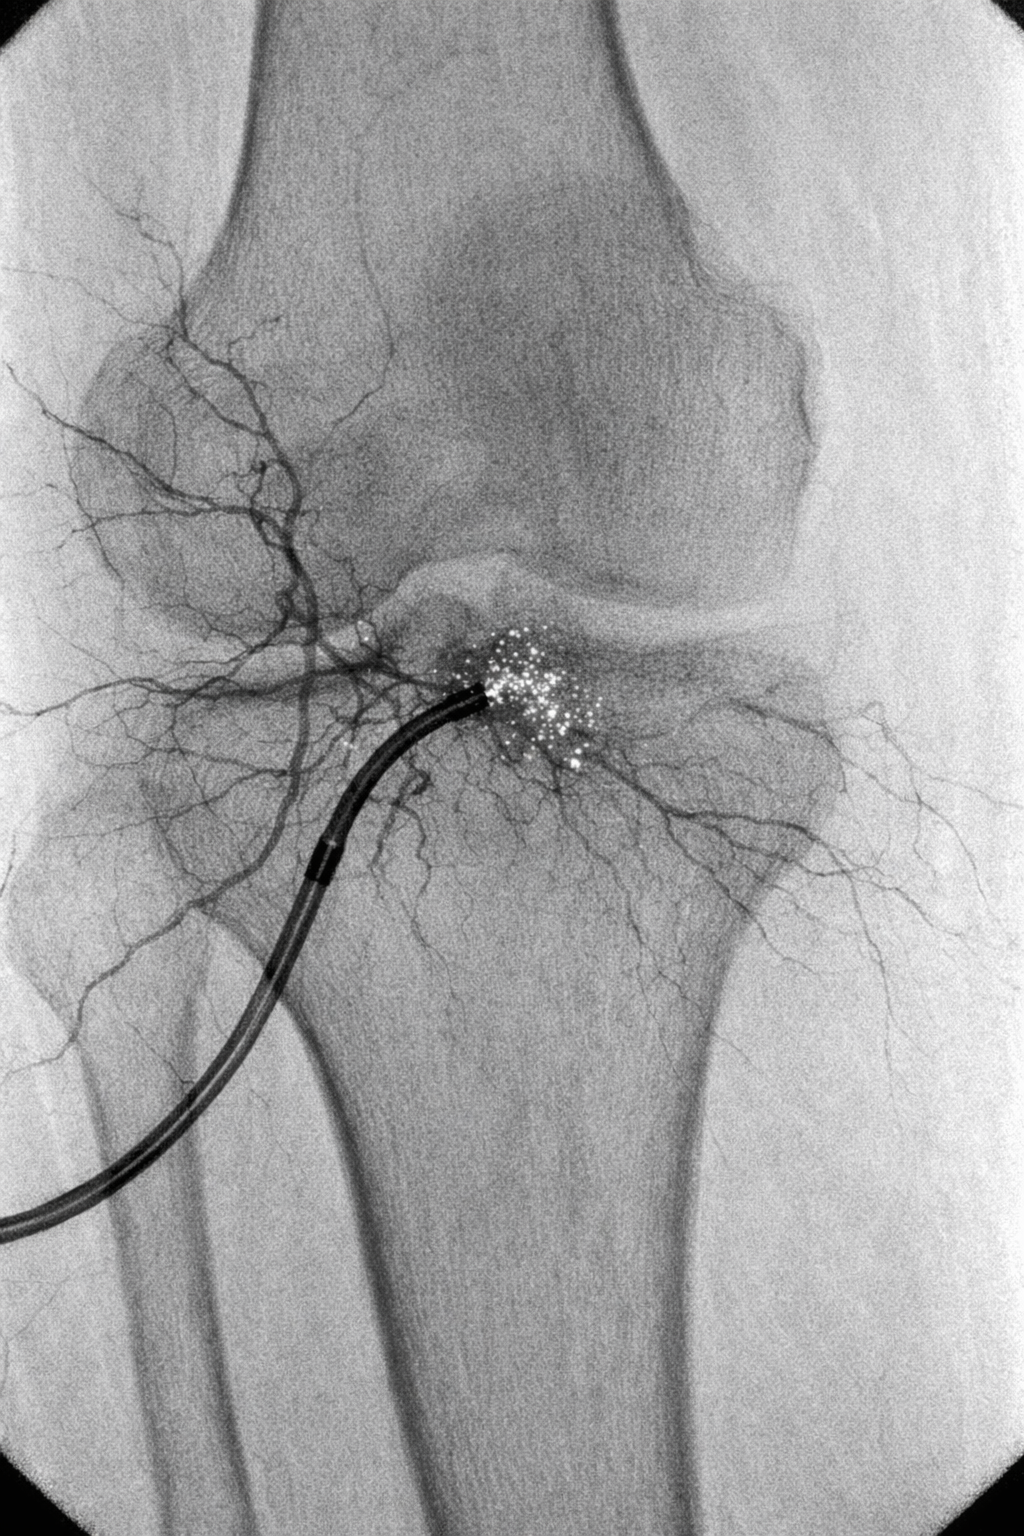

In the course of GAE:

A tiny hole in the artery is used to implant a tiny catheter.

The physician finds the arteries that supply the inflammatory knee tissue.

To stop aberrant blood flow, certain tiny particles are administered.

This lessens inflammation and provides non-surgical relief from persistent knee discomfort.